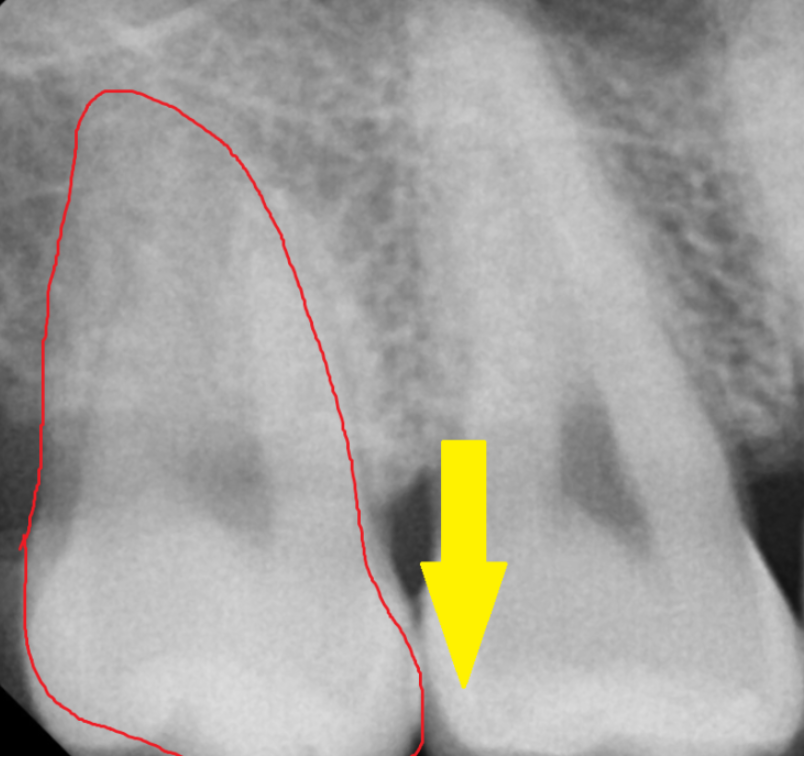

위에 사랑니는 아래뼈에 비하여

뼈도 약하고

똑바로 나온 경우가 많아서

발치 난이도가 쉬운편입니다.

관리가 잘되면 그냥 두지만

잇몸 통증이 있거나

불편하실 때에는 발치를 추천드리는데요.